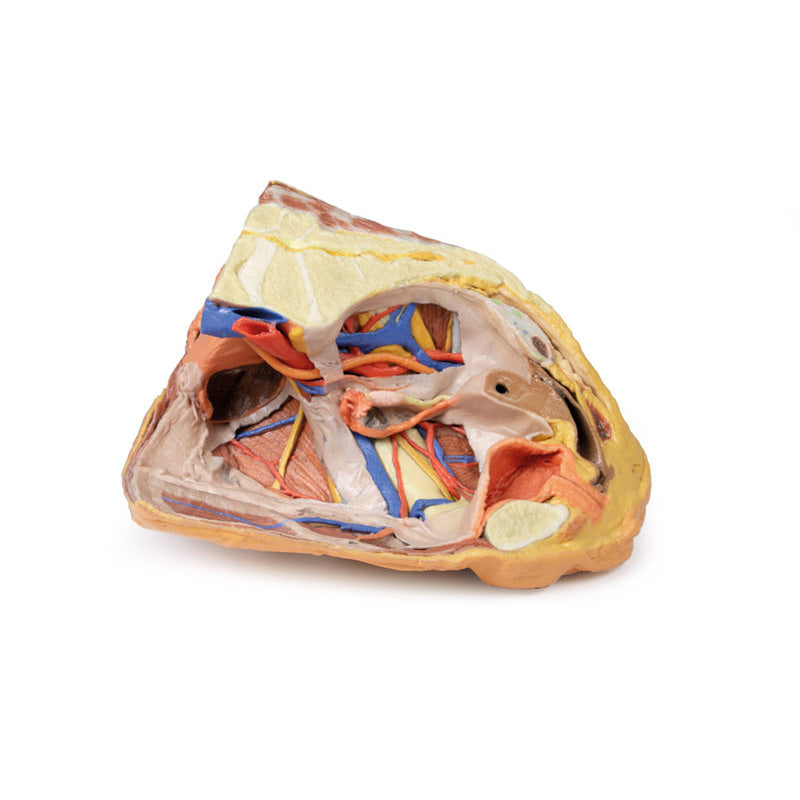

3D Printed Female right pelvis superficial and deep structures

The specimen has been sectioned transversely through the L4 vertebra, displaying a cross section of the colon, the epaxial musculature (psoas and quadratus lumborum muscles), and the abdominal wall musculature. The common iliac artery has been preserved from the level of the L4 vertebra, and its bifurcation into the external and internal iliac arteries can be observed at the level of the sacral promontory. Deep to the arteries the common iliac vein and the origin of the inferior vena cava are visible.

The external iliac artery and vein passes anteroinferiorly along the pelvic brim, giving rise to the inferior epigastric and deep circumflex arteries and veins before passing deep to the inguinal ligament. The psoas major muscle lies lateral to the external iliac artery, with the femoral nerve evident on its lateral margin close to the inguinal ligament. The lateral cutaneous nerve of the thigh travels laterally on the superficial surface of the iliacus muscle to exit the ‘false’ pelvis close to the anterior superior iliac spine.

Following the course of the internal iliac artery deep to the undissected peritoneum, many of the major branches of its anterior and posterior divisions can be identified. The anterior division divides (deep to the peritoneum) into the superior vesical, obturator and obliterated umbilical artery. With a course parallel to the obturator artery, the obturator nerve can be seen running over obturator internus before entering the obturator canal together with the obturator vein (nerve, artery, vein in that order from superior to inferior).

Branches of the posterior division of the internal iliac artery, iliolumbar, and several lateral sacral arteries, can be seen arising from the posterior aspect of the internal iliac just below the sacral promontory. Its terminal branch, the superior gluteal, usually passes posteriorly between the lumbosacral trunk and S1 nerve, but this is hidden from view. The internal iliac vein and its tributaries - the obturator veins, uterine vein, vesical veins, etc. can be seen lying internal to the nerves and muscles. The large S1 and S2 roots and the smaller S3 nerve root can be seen emerging from the sacral foramina to pass laterally where it is joined by the lumbosacral trunk (L4 and l5 roots) which is not visible, to form the sciatic nerve which exits through the greater sciatic foramen to emerge on the posterior aspect in the gluteal region. In the pelvis as these roots pass laterally they are interdigitated between the fibres of piriformis muscle.

The right ureter can be clearly seen as it passes inferiorly on the posterior abdominal wall superficial to psoas muscle. It passes over the pelvic brim at the bifurcation of the common iliac artery to descend on the lateral wall of the pelvis before passing medially in the base of the broad ligament (hidden from view as the peritoneal folds that ‘drape’ over the uterine [Fallopian] tubes are still intact) to reach the lateral angles of the bladder. In the pelvis the viscera which lies most anteriorly is the bladder. Its thick wall and cavity is easily seen in this mid-sagittal cut. Indeed the ureteric orifice can be seen at the angle of the trigone of the bladder on its internal mucosal surface. The relations of the uterus to the vagina are clearly visible in the mid-sagittal section. Indeed the anterior and posterior fornices are clearly seen as is the os of the cervix. The round ligament of the uterus has been removed along with some peritoneum to display the structures in the lateral pelvic wall. The entire right Fallopian tube is identifiable as it passes from the lateral aspect of the body of the uterus to terminate as the fimbria which overhangs the right ovary which is still held in place by its mesovarium. The ovary is attached laterally to the pelvic brim by the suspensory ligament of the ovary (sometimes called the infundibulopelvic ligament) which contains its named artery and veins. The ligament of the ovary is clearly visible leading from the medial aspect of the ovary to the lateral surface of the uterus.

There are only small cut surfaces of the rectum (visible as little islands of mucosa) visible on the sagittal cut surface suggesting that it is slightly off the midline plane. Some pararectal lymph nodes (coloured pale green) can be seen close to these islands of rectal mucosa. On the anterior aspect of the 3D print the inguinal ligament has been retained and deep to it the femoral artery, vein and nerve pass to the anterior compartment of the thigh.

In the gluteal region (note the femur has been removed to expose the acetabulum) the sciatic nerve can be seen emerging from the greater sciatic foramen (GSF) alongside the inferior gluteal vessels below the remains of the piriformis fibres, whereas the superior gluteal vessels and nerve emerges above the piriformis. Below these vessels the pudendal nerves and vessels can be seen exiting the GSF and passing over the sacrospinous ligament to enter the lesser sciatic foramen, thereby entering the perineum along the lateral wall of the ischioanal fossa.

3D Printed Female right pelvis superficial and deep structures

This 3D printed female right pelvis preserves both superficial and deep structures of the true and false pelves, as well as the inguinal ligament, the obturator membrane and canal, and both the greater and lesser sciatic foramina. Somewhat unique is the removal of portions of the peritoneum (a grayish colour) to create ‘windows’ displaying extraperitoneal structures.The specimen has been sectioned transversely through the L4 vertebra, displaying a cross section of the colon, the epaxial musculature (psoas and quadratus lumborum muscles), and the abdominal wall musculature. The common iliac artery has been preserved from the level of the L4 vertebra, and its bifurcation into the external and internal iliac arteries can be observed at the level of the sacral promontory. Deep to the arteries the common iliac vein and the origin of the inferior vena cava are visible.

The external iliac artery and vein passes anteroinferiorly along the pelvic brim, giving rise to the inferior epigastric and deep circumflex arteries and veins before passing deep to the inguinal ligament. The psoas major muscle lies lateral to the external iliac artery, with the femoral nerve evident on its lateral margin close to the inguinal ligament. The lateral cutaneous nerve of the thigh travels laterally on the superficial surface of the iliacus muscle to exit the ‘false’ pelvis close to the anterior superior iliac spine.

Following the course of the internal iliac artery deep to the undissected peritoneum, many of the major branches of its anterior and posterior divisions can be identified. The anterior division divides (deep to the peritoneum) into the superior vesical, obturator and obliterated umbilical artery. With a course parallel to the obturator artery, the obturator nerve can be seen running over obturator internus before entering the obturator canal together with the obturator vein (nerve, artery, vein in that order from superior to inferior).

Branches of the posterior division of the internal iliac artery, iliolumbar, and several lateral sacral arteries, can be seen arising from the posterior aspect of the internal iliac just below the sacral promontory. Its terminal branch, the superior gluteal, usually passes posteriorly between the lumbosacral trunk and S1 nerve, but this is hidden from view. The internal iliac vein and its tributaries - the obturator veins, uterine vein, vesical veins, etc. can be seen lying internal to the nerves and muscles. The large S1 and S2 roots and the smaller S3 nerve root can be seen emerging from the sacral foramina to pass laterally where it is joined by the lumbosacral trunk (L4 and l5 roots) which is not visible, to form the sciatic nerve which exits through the greater sciatic foramen to emerge on the posterior aspect in the gluteal region. In the pelvis as these roots pass laterally they are interdigitated between the fibres of piriformis muscle.

The right ureter can be clearly seen as it passes inferiorly on the posterior abdominal wall superficial to psoas muscle. It passes over the pelvic brim at the bifurcation of the common iliac artery to descend on the lateral wall of the pelvis before passing medially in the base of the broad ligament (hidden from view as the peritoneal folds that ‘drape’ over the uterine [Fallopian] tubes are still intact) to reach the lateral angles of the bladder. In the pelvis the viscera which lies most anteriorly is the bladder. Its thick wall and cavity is easily seen in this mid-sagittal cut. Indeed the ureteric orifice can be seen at the angle of the trigone of the bladder on its internal mucosal surface. The relations of the uterus to the vagina are clearly visible in the mid-sagittal section. Indeed the anterior and posterior fornices are clearly seen as is the os of the cervix. The round ligament of the uterus has been removed along with some peritoneum to display the structures in the lateral pelvic wall. The entire right Fallopian tube is identifiable as it passes from the lateral aspect of the body of the uterus to terminate as the fimbria which overhangs the right ovary which is still held in place by its mesovarium. The ovary is attached laterally to the pelvic brim by the suspensory ligament of the ovary (sometimes called the infundibulopelvic ligament) which contains its named artery and veins. The ligament of the ovary is clearly visible leading from the medial aspect of the ovary to the lateral surface of the uterus.

There are only small cut surfaces of the rectum (visible as little islands of mucosa) visible on the sagittal cut surface suggesting that it is slightly off the midline plane. Some pararectal lymph nodes (coloured pale green) can be seen close to these islands of rectal mucosa. On the anterior aspect of the 3D print the inguinal ligament has been retained and deep to it the femoral artery, vein and nerve pass to the anterior compartment of the thigh.

In the gluteal region (note the femur has been removed to expose the acetabulum) the sciatic nerve can be seen emerging from the greater sciatic foramen (GSF) alongside the inferior gluteal vessels below the remains of the piriformis fibres, whereas the superior gluteal vessels and nerve emerges above the piriformis. Below these vessels the pudendal nerves and vessels can be seen exiting the GSF and passing over the sacrospinous ligament to enter the lesser sciatic foramen, thereby entering the perineum along the lateral wall of the ischioanal fossa.